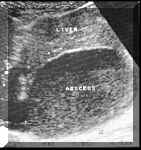

Recently formed amoebic abscesses :

An abscess of recent onset has a distinct central liquified area. This is seen on ultrasound as a sonolucent or an hypoechoic area usually with fine internal echoes. Because of the liquefaction, there is associated posterior acoustic enhancement. The cavity may be round, oval or branching. The walls of the abscess at this stage are usually not very thick and sometimes the demarcation between the wall and the surrounding tissue can be poor. Sometimes the walls may be thicker and these may be seen as shaggy, ill-defined echogenic areas along the walls

(see Picture2). It is at this stage of the abscess that aspiration may be required. Small amount of air in the abscess because of secondary infection or following an aspiration is seen as highly reflective dots.

Picture2.

It is at this stage of the abscess that differential diagnosis of a cyst in the liver, a cyst with haemorrhage, cystic metastatic deposit or sometimes a hydatid cyst and haematoma are to be considered.